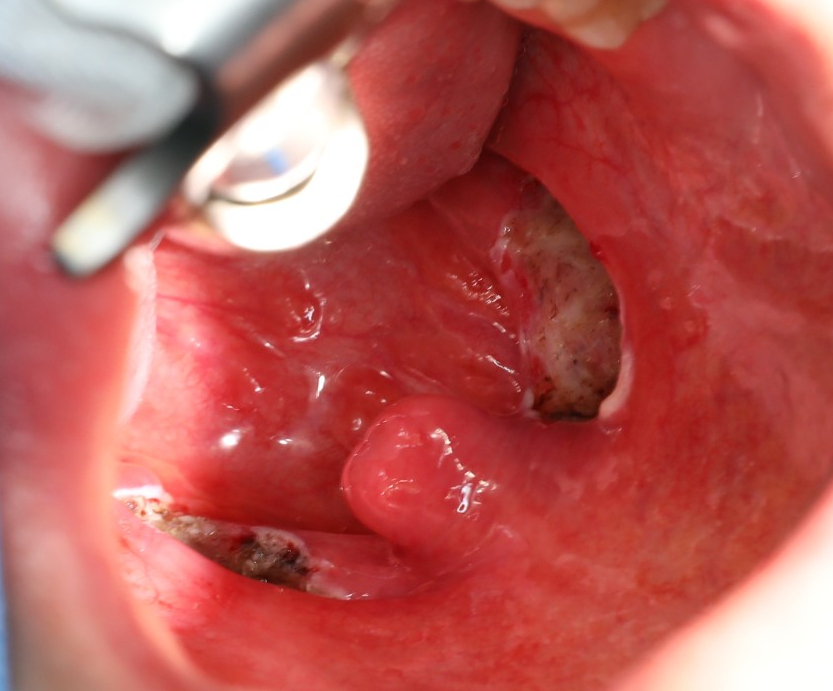

수술은 전신 마취로 이루어졌습니다. 편도전 절제술은 반드시 전신 마취로 수술을 받아야 합니다.

편도를 절제하는 여러 가지 도구가 있습니다. 그 중에서 환자가 선택한 수술 도구는 코브레터였습니다.

편도완전절제술 TOTALTONSILLECTOMY

편도 결석이 있는 분은 대부분 만성 편도염을 앓는 경우가 많기 때문에 수술 중 출혈이 많지요. 다행히 오늘 환자는 출혈이 많지 않았어요. 대부분 코브레터 편도 절제술은 출혈이 많지 않으면 양측 절제에 15분에서 30분 정도 걸립니다.

이 환자의 경우 심부 60% 정도에 이르기까지 편도 내에 다량의 결석이 존재하고 있었습니다. 수술하면서 편도를 잡고 누를 때 상당한 양의 편도 결석이 밖으로 튀어나왔습니다.